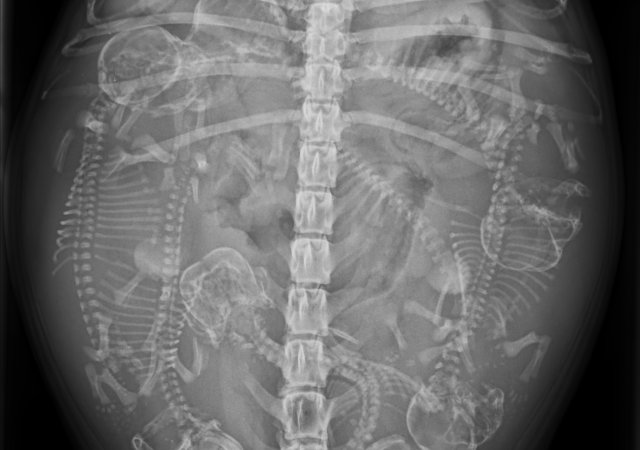

• Routinierte Kastration (weiblich/männlich) aller Tierarten, auch aller Heimtierarten (Kaninchen, Meerschweinchen und co.), insbesondere auch weiblicher Heimtiere